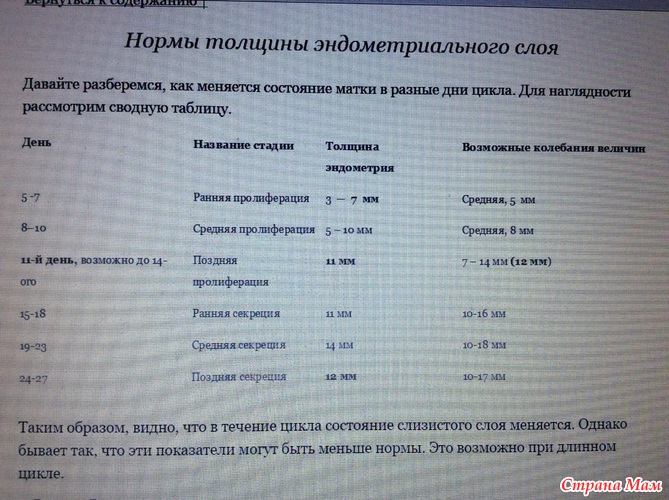

Эндометрий и Беременность: Что Нужно Знать